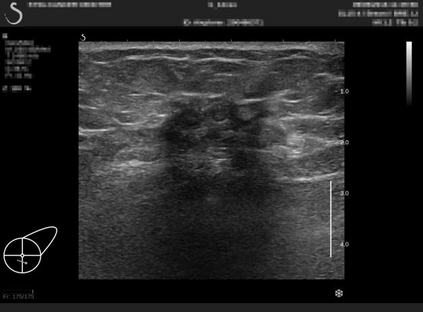

Ultrasonography is an important routine examination for breast cancer diagnosis, due to its non-invasive, radiation-free and low-cost properties. However, it is still not the first-line screening test for breast cancer due to its inherent limitations. It would be a tremendous success if we can precisely diagnose breast cancer by breast ultrasound images (BUS). Many learning-based computer-aided diagnostic methods have been proposed to achieve breast cancer diagnosis/lesion classification. However, most of them require a pre-define ROI and then classify the lesion inside the ROI. Conventional classification backbones, such as VGG16 and ResNet50, can achieve promising classification results with no ROI requirement. But these models lack interpretability, thus restricting their use in clinical practice. In this study, we propose a novel ROI-free model for breast cancer diagnosis in ultrasound images with interpretable feature representations. We leverage the anatomical prior knowledge that malignant and benign tumors have different spatial relationships between different tissue layers, and propose a HoVer-Transformer to formulate this prior knowledge. The proposed HoVer-Trans block extracts the inter- and intra-layer spatial information horizontally and vertically. We conduct and release an open dataset GDPH&GYFYY for breast cancer diagnosis in BUS. The proposed model is evaluated in three datasets by comparing with four CNN-based models and two vision transformer models via a five-fold cross validation. It achieves state-of-the-art classification performance with the best model interpretability.

翻译:超声波分析是乳腺癌诊断的一个重要常规检查,原因是其非侵入性、无辐射和低成本的特性。然而,由于其内在局限性,它仍不是乳腺癌的第一线筛选测试。如果我们能够精确地通过乳房超声图像诊断乳腺癌(BUS),它将是一个巨大的成功。我们提出了许多基于学习的计算机辅助诊断方法,以实现乳腺癌诊断/感官分类。然而,其中多数方法需要事先确定性能模型,然后对ROI内部的跨值进行分类。常规分类支柱,如VGG16和ResNet50等,可以在没有ROI要求的情况下实现有希望的分类结果。但是这些模型缺乏可解释性,从而限制了其在临床实践中的使用。在本研究中,我们提出了一个新的无乳腺癌诊断模型,在超声波图像中进行解释性特征描述。我们利用了先前的解剖学学学知识,即恶性肿瘤和良性肿瘤模型在不同组织层之间有着不同的空间关系,并提议采用状态解析法来编制这一先前的知识。拟议中的HOVer-Trans-Trading-Tradef-trainal Ex-deal-dealal-deal-deal-deal-degraphal-deal-deal-deal-deal-deal-deal disal disal-dal-dal-dal-dal-dal-deal-deal-dal-deal-deal-deal-dal-dal-dal-dal-dal-dal-dal-dal-dal-dal-dal-dal-dal-dal-I-dal-Iversal-dal-Ial-d-d-I-d-d-I-I-I-I-I-I-I-I-I-I-I-I-I-I-I-I-I-I-I-I-I-I-I-I-I-Ial-I-Ial-Ial-I-I-I-I-I-I-I-I-I-I-I-I-I-I-I-I-I-I-I-I-I-I-I-I-I-I-I-I-I-I-I-I-